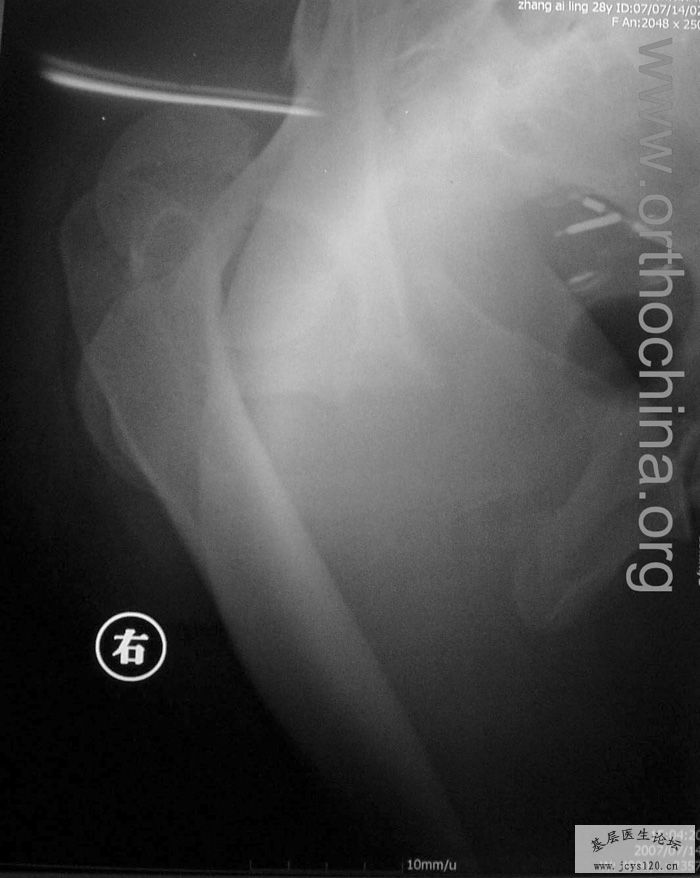

患者,女,28岁,车祸中骨盆轧伤后疼痛功能障碍1小时。查体:休克外貌,烦躁不安。头颈胸腹无异常,脊柱无异常,两下肢血供及感觉正常。骨盆挤压分离试验阳性。阴道、尿道、直肠、腹内脏器无损伤。住院后抗休克、骨牵引及对症治疗1周后,行前后联合入路手术。股骨头骨折复位后用可吸收螺钉固定,骶髂关节、髋臼前后柱、对侧耻骨上下支用骨盆重建钛板固定,术中出血1200ML,手术时间8小时。部分图片如下: